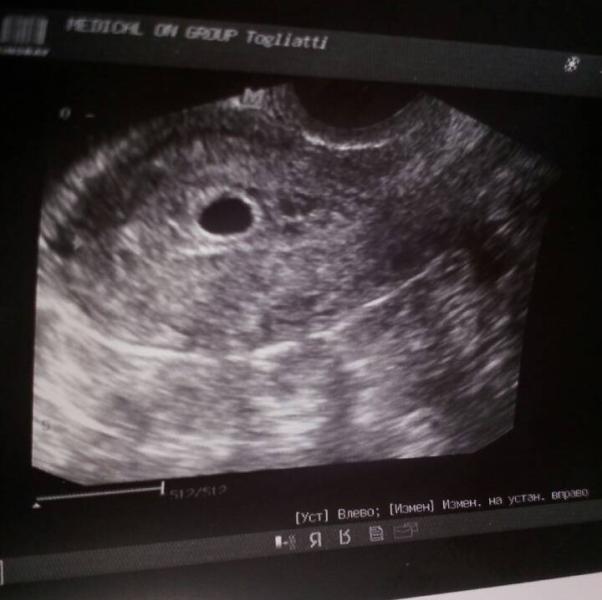

Всем привет! Девчули, чё то я в панике... Сделала вчера узи, маточная беременность 3-4 недели. размер плодного яйца 12мм, желточный мешочек 4,2 мм., сердцебиения нет. Перерыла интернет, не соответствии размера плодного яйца 12 мм —4,5-7,5 недель. Может ЗБ? ,или узист неправильно проставила размеры, или ошиблась в сроке? Делала узи в медикал он групп.

желточный мешочек если есть,значит все нормально😊мне на 5-6 тоже ничего не сказали,а через неделю уже сердцебиение послушала!

У меня в 3-4 недели было плодное яйцо, а сердцебиение появилось на 7-8 недели! Не паникуйте!

для 5 недель все так и должно быть. не раньше чем через 2 недели идите и увидите серцебиение!

Сердцебиение появляется на 6-7 неделе. Не паникуйте. У знакомой вообще в 9 увидели..Все хорошо у вас! 🌺